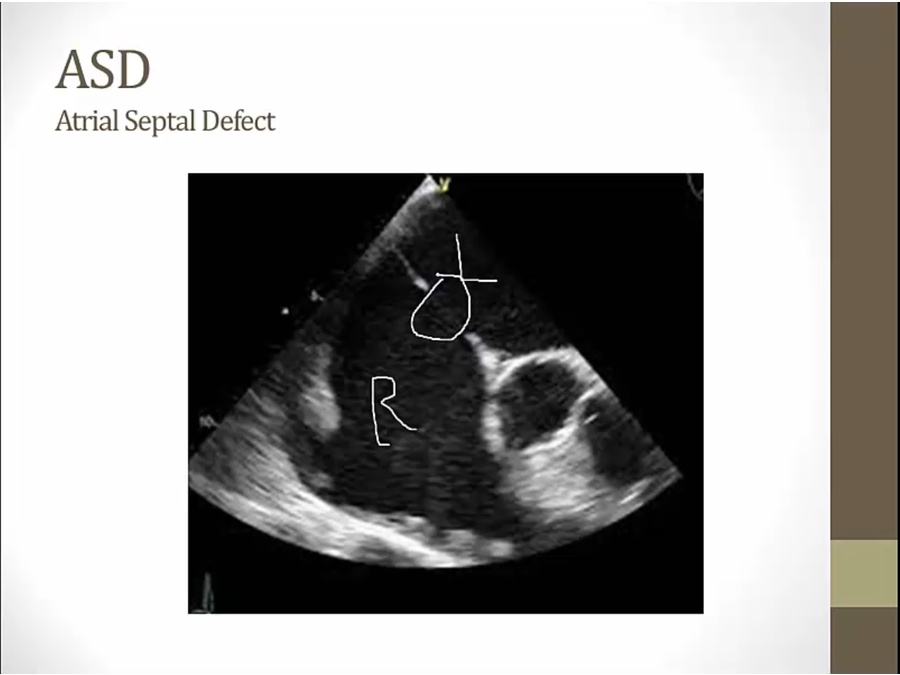

ASD

major consequence: add volume to right side of heart

increased flow across PV/TV causes systolic ejection murmur

echo: RA on left, LA on right